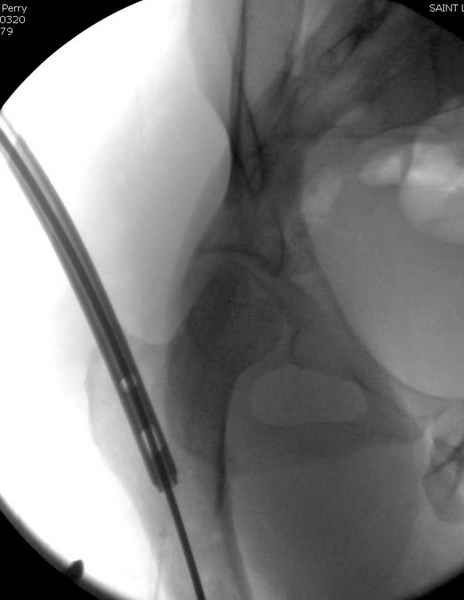

Как раз недавно у меня был примерный случай: больному 36 лет, поступил ночью, травма в результате мотоциклетной аварии, кроме чрезвертельного и спирального перелома левого бедра имеется переломы костей предплечья с этой же стороны. Скелетное вытяжение, а на следующий день больной про оперирован на ортопедическом столе с дистракцией. Чтобы не расколоть чрезвертельный перелом провели временную спицу ближе к переднему кортексу, из малого разреза костодержатель для репозиции, а фиксацию провели антиградным штифтом. Этапы операции на снимках.

Второй случай тоже репозиция из малого доступа, больному 19 лет, множественные огнестрельные повреждениия конечностей, живота и черепа, правая конечность холодная, без пульсации. Ортопедический диагноз: огнестрельный перелом правого бедра. При срочной ангиографии повреждения сосудов не подтвердилось, конечность из-за ургентности состояния больного зафиксирована временным наружным фиксатором и больной оставлен на операционном столе для срочной лапаротомии хирургической службой.

Больной долго оставался нестабильным, только на 14 день удалось заменить на антеградный интромедуллярный штифт TFN (trochanteric femoral nail) SmithNephew. После неудачной попытки закрытой репозиции, несмотря на использование "joystick", проксимальный стержень от

наружного фиксатора, (перелом начал срастаться) репозицию провели из малого доступа, затем остальные этапы операции.